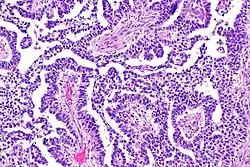

The ovarian yolk sac tumors, also known as endodermal sinus tumors, are accountable for approximately 15.5% of all OGCTs.[8] They have been observed in women particularly in their early ages, and rarely after 40 years of age.[9] The critical pathologic features are a smooth external surface and capsular tears due to their rapid rate of growth. A study consisting of 71 individual cases of ovarian yolk sac tumor provides evidence to the proliferation of the tumor. In one of the cases, the pelvic examination revealed normal activity until a 9 cm and 12 cm sized tumor was discovered 4 weeks later.[9] In another case, a 23 cm tumor was discovered in a pregnant woman who was monitored regularly and had normal findings until oophorectomy became essential.[9] Histologically, these tumors are characterized by mixed solid and cystic components.[1] The mixed solid components are characterized by a soft gray to yellow solid components accompanied with significant hemorrhage and necrosis. The cysts are approximately 2 cm in diameter and populated throughout the tissue which results in giving the neoplasm a ‘honeycombed appearance’.[1]